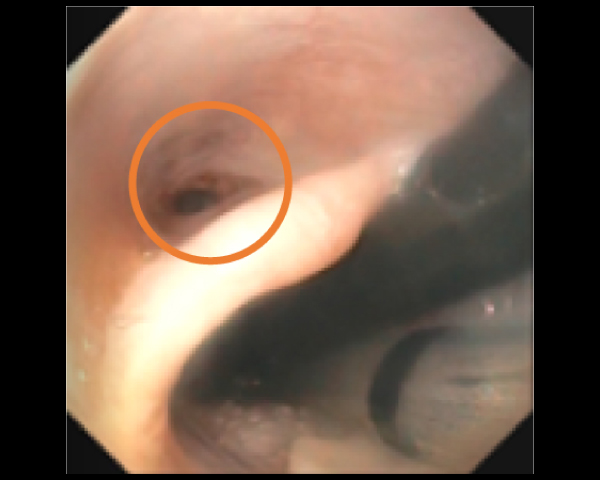

内視鏡で狭窄部位を確認